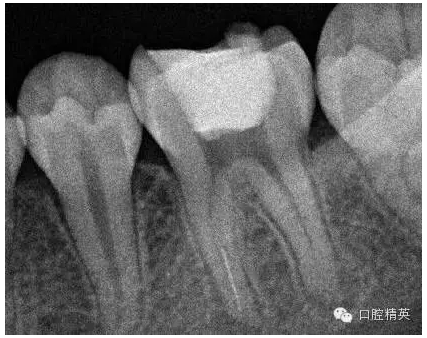

3,術(shù)前左下6近中根管斷針X-P,斷針長度約4MM,根尖慢性炎癥影像。。。